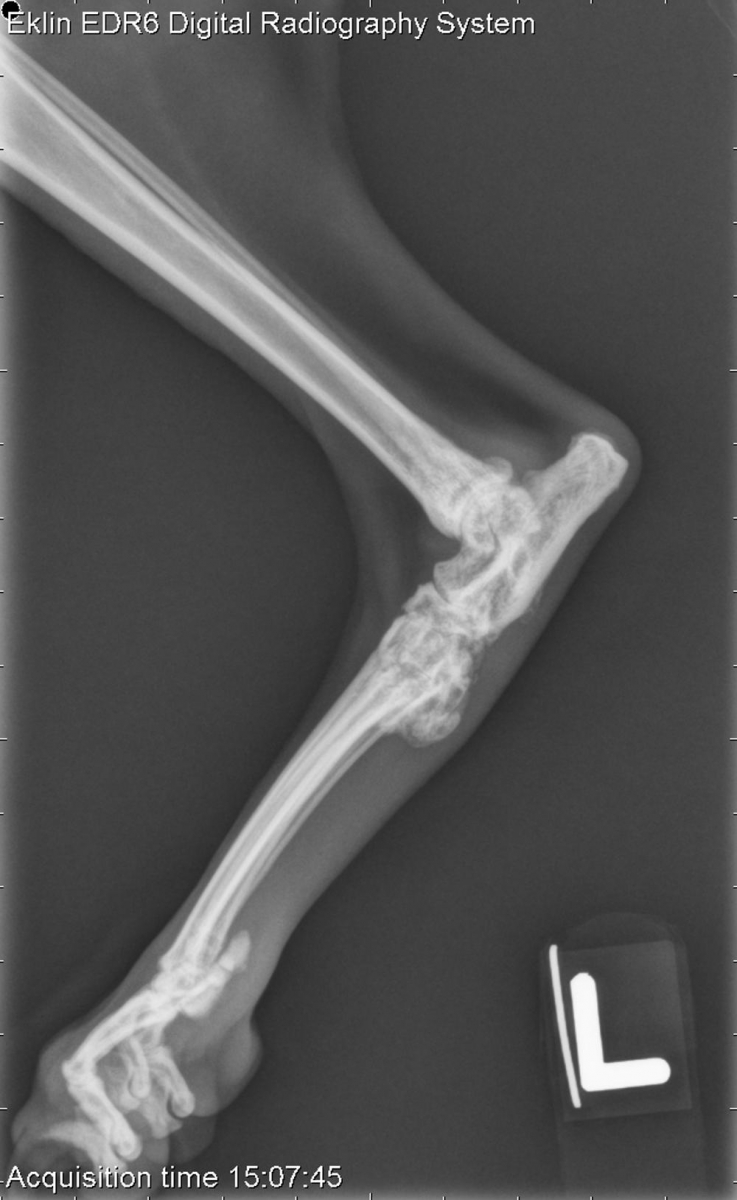

6 year old DMH cat Cat Tarsal Joint Anatomy Tarsal joint includes joints between crural, tarsal and metatarsal bones. The feline and canine manus differ a little as cats do not The tarsal joint of these species is considerably complex, as it is constituted by the tibia, fibula, tarsal bones, metatarsal bones and the ligaments and fibrocartilage. The carpus has a complex anatomy, with seven carpal and five metacarpal. Cat Tarsal Joint Anatomy.